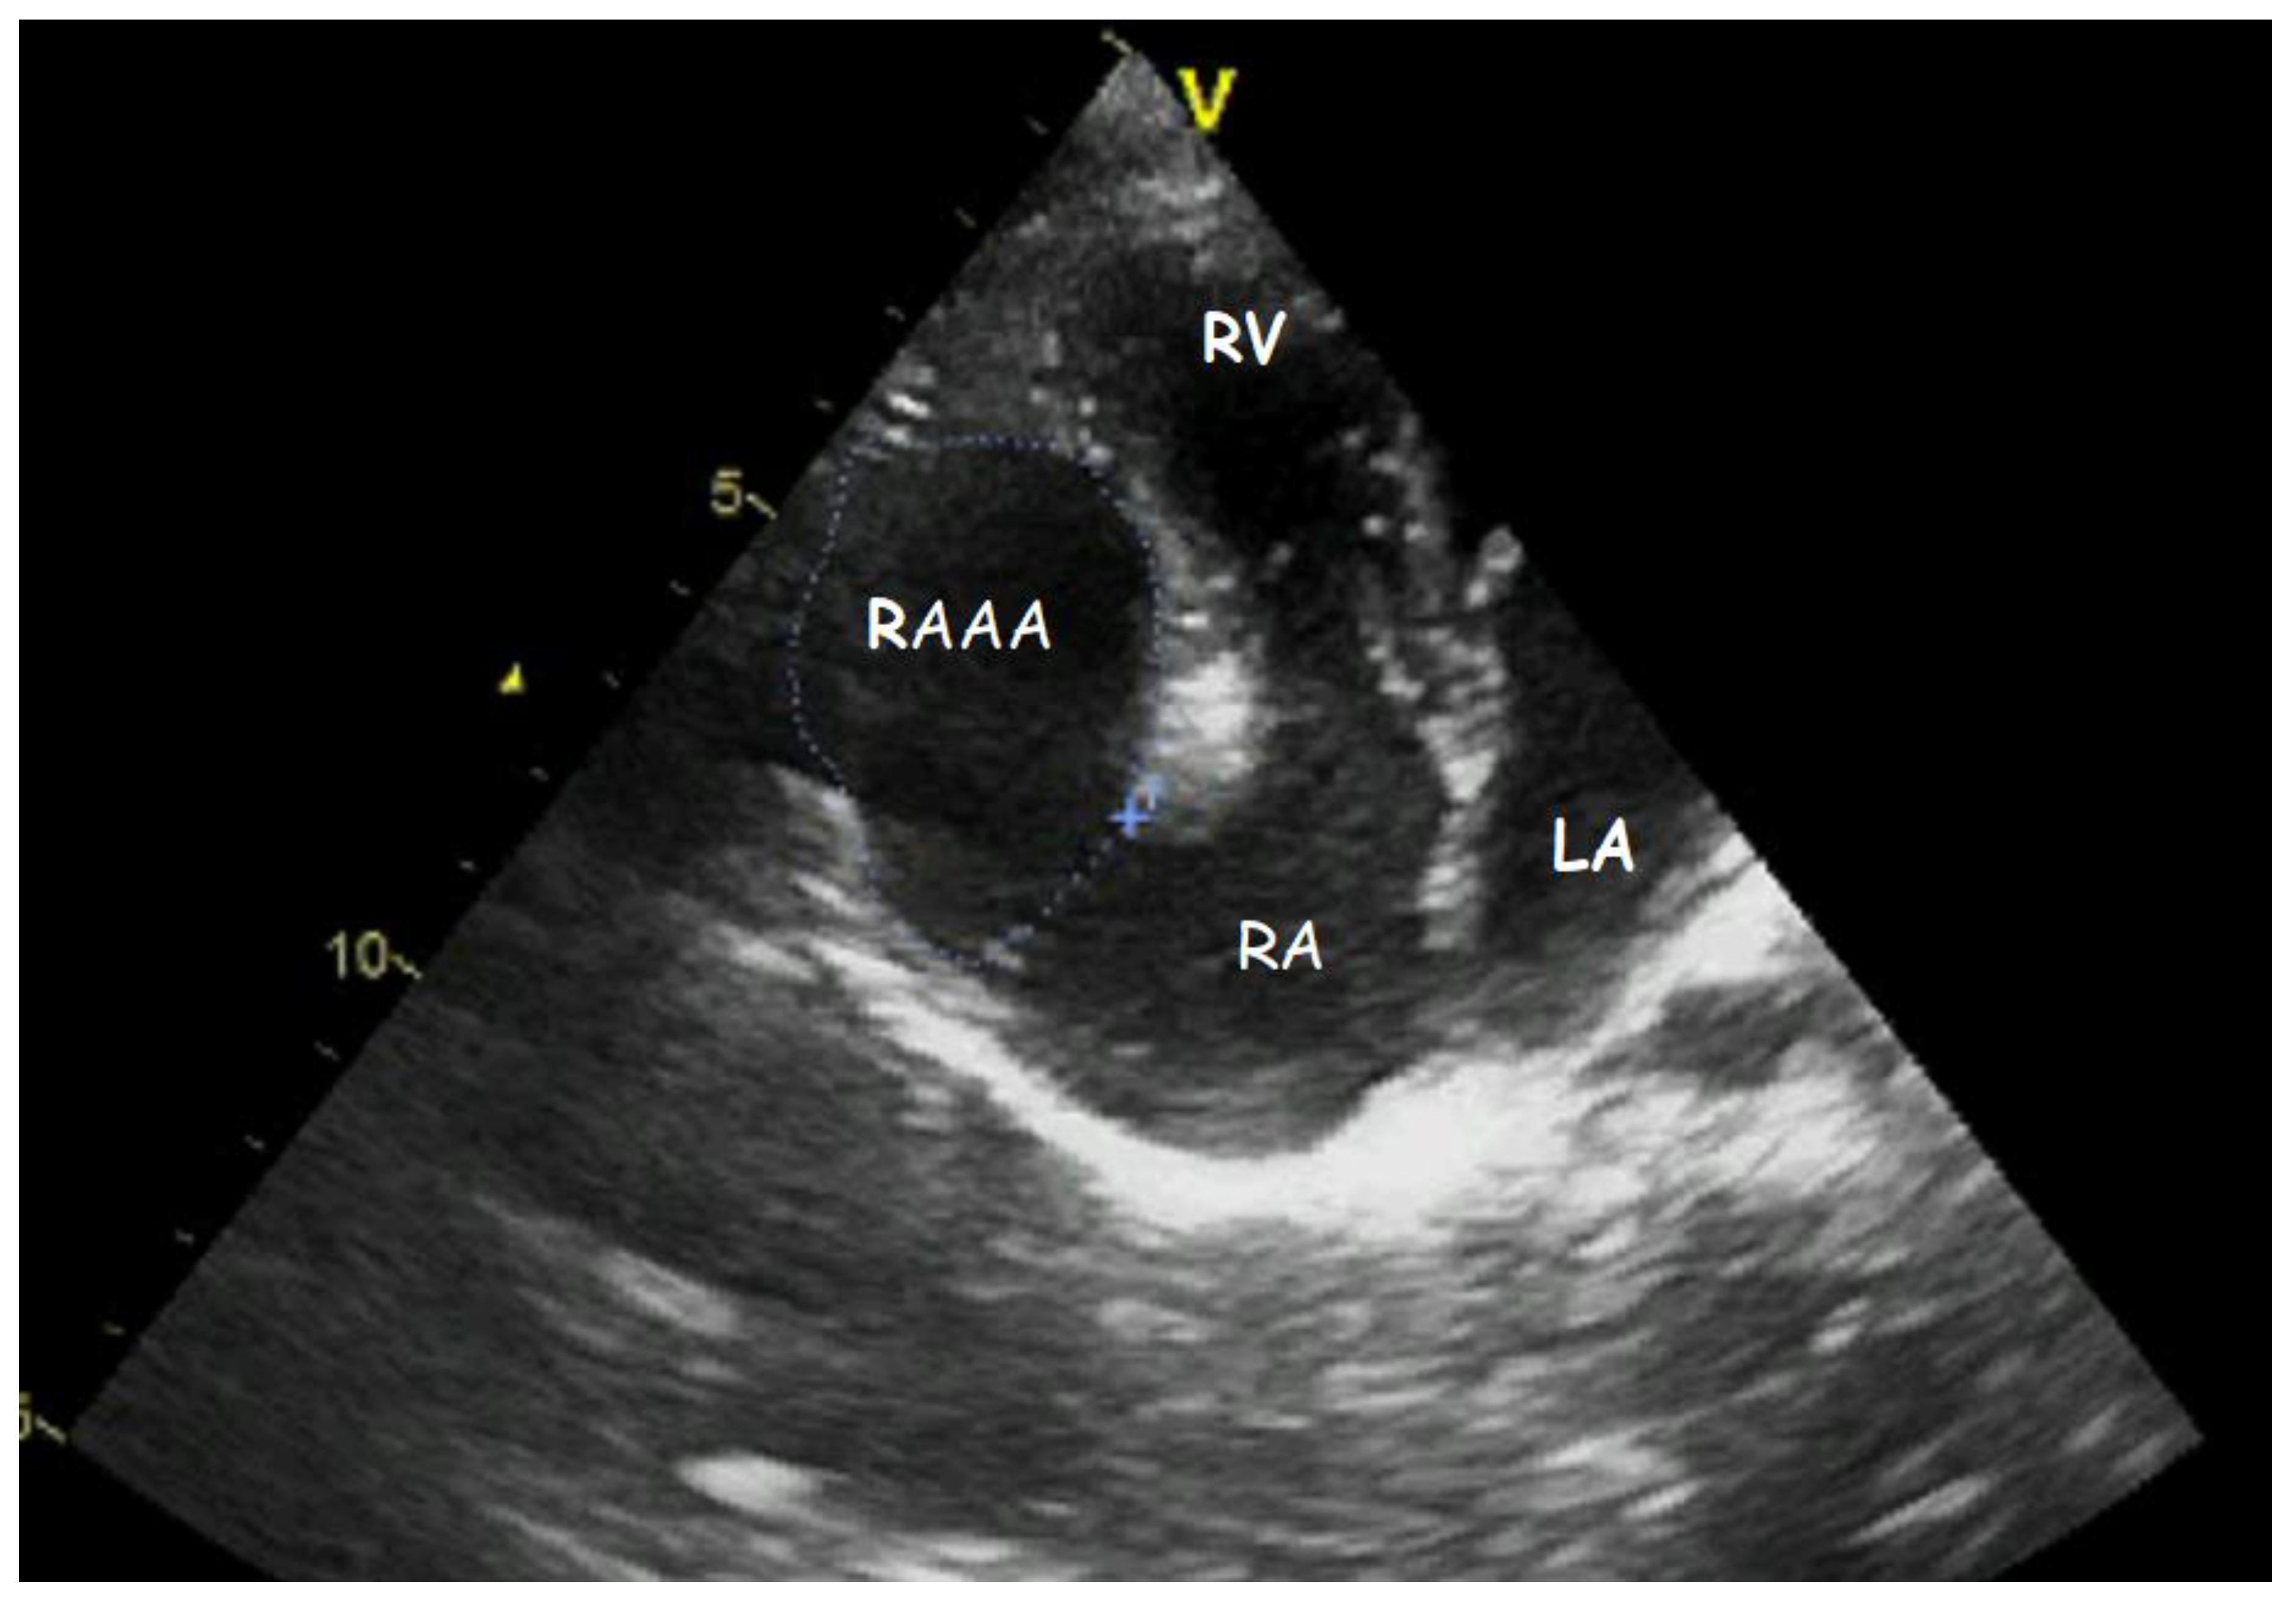

A Gigantic Congenital Right Atrial Appendage Aneurysm in an Infant: Ten-Year Follow-Up

1. Clinical Presentation